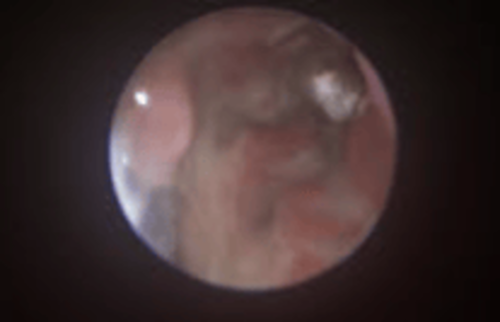

Pilzplaque in der Stirnhöhle mit ausgeprägter Nasenmuschelzerstörung